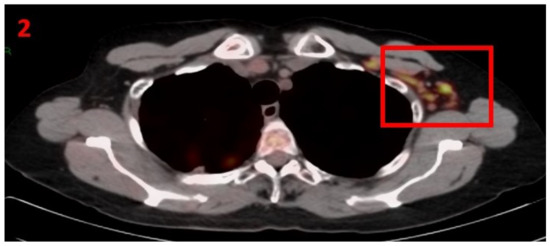

3.2. Case No 2

| Case no.2 | Breast cancer | Left arm | 7 days | Hypermetabolic uptake in the left axillary region and lymphadenopathy | First vaccine | 7 mm | 3.7 | Pfizer-BioNTech |